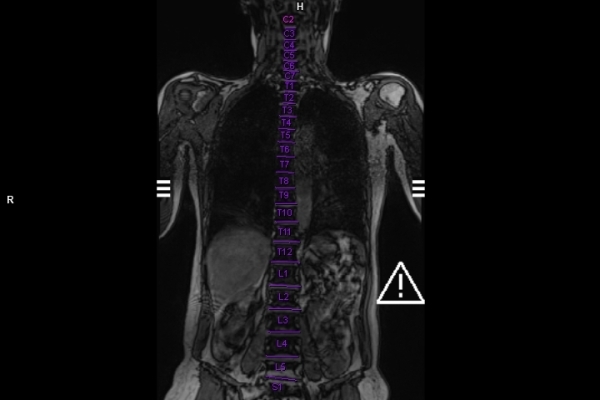

CT Untersuchung Bild

Detailbild MRT